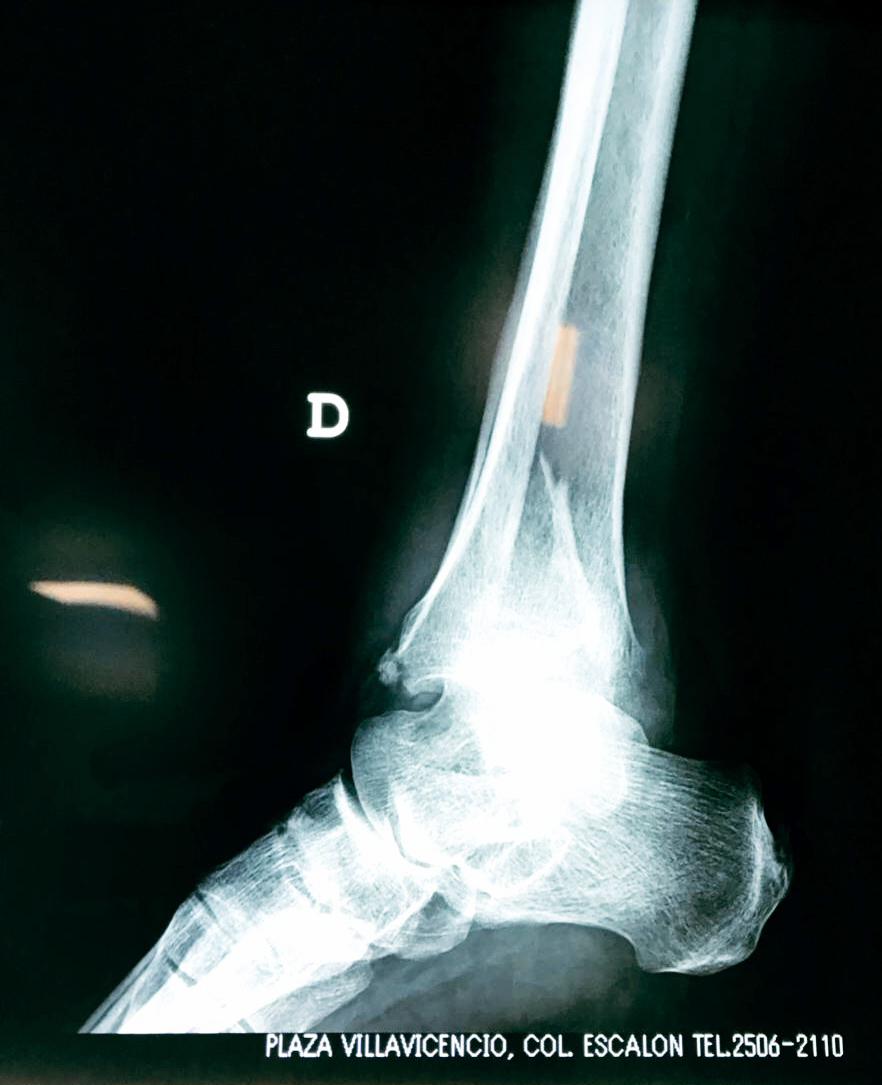

Astrágalo Tobil...

Detail Download